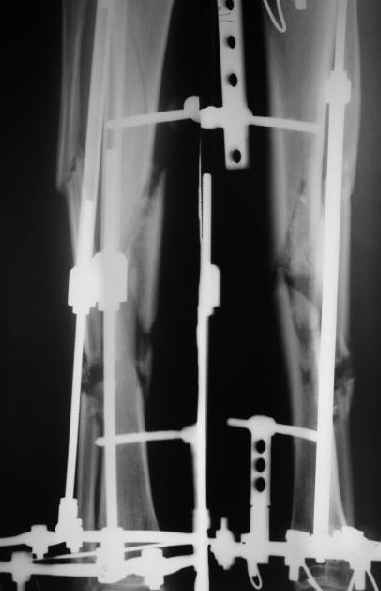

Re: ресинтез

Сергей Зырянов 10 Апрель 2004, 19:43

1

2

Пациент вернулся. Результаты лечения удовлетворяют его.

Буду продолжать наблюдать, лечить.

Раны зажили хорошо, швы снял. Сделали контрольный рентгеновский снимок бедра. Движения в коленном суставе востанавливаются, угол 94 гр.

Больной ходит пока с костылями, с неполной нагрузкой весом тела, он боится больше нагружать.